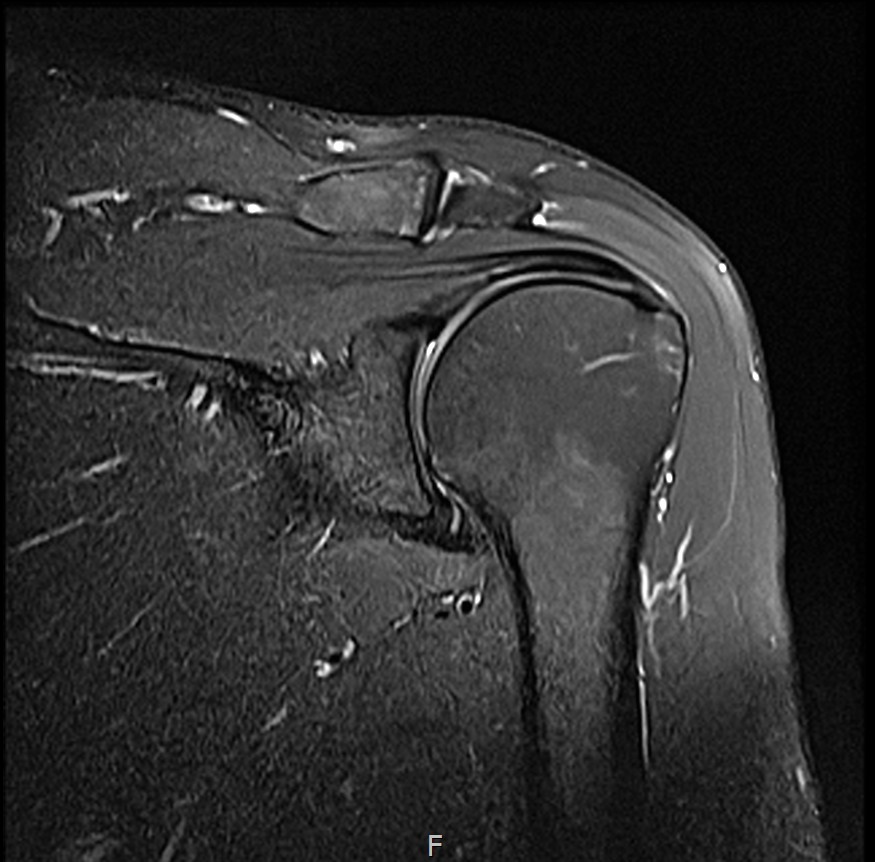

MRI를 검토해보았습니다.

회전근개 극상건의 점액낭면측(bursal-side) 부분파열. 처음보다 파열 범위가 약간 넓어져 있었고, 인대가 얇아진 소견도 보였습니다.

MRI: 극상건 점액낭면측 부분파열

인대 두께: 4.2mm (정상 5~6mm보다 얇음)

1년간 주사치료 3회, 반복 재발